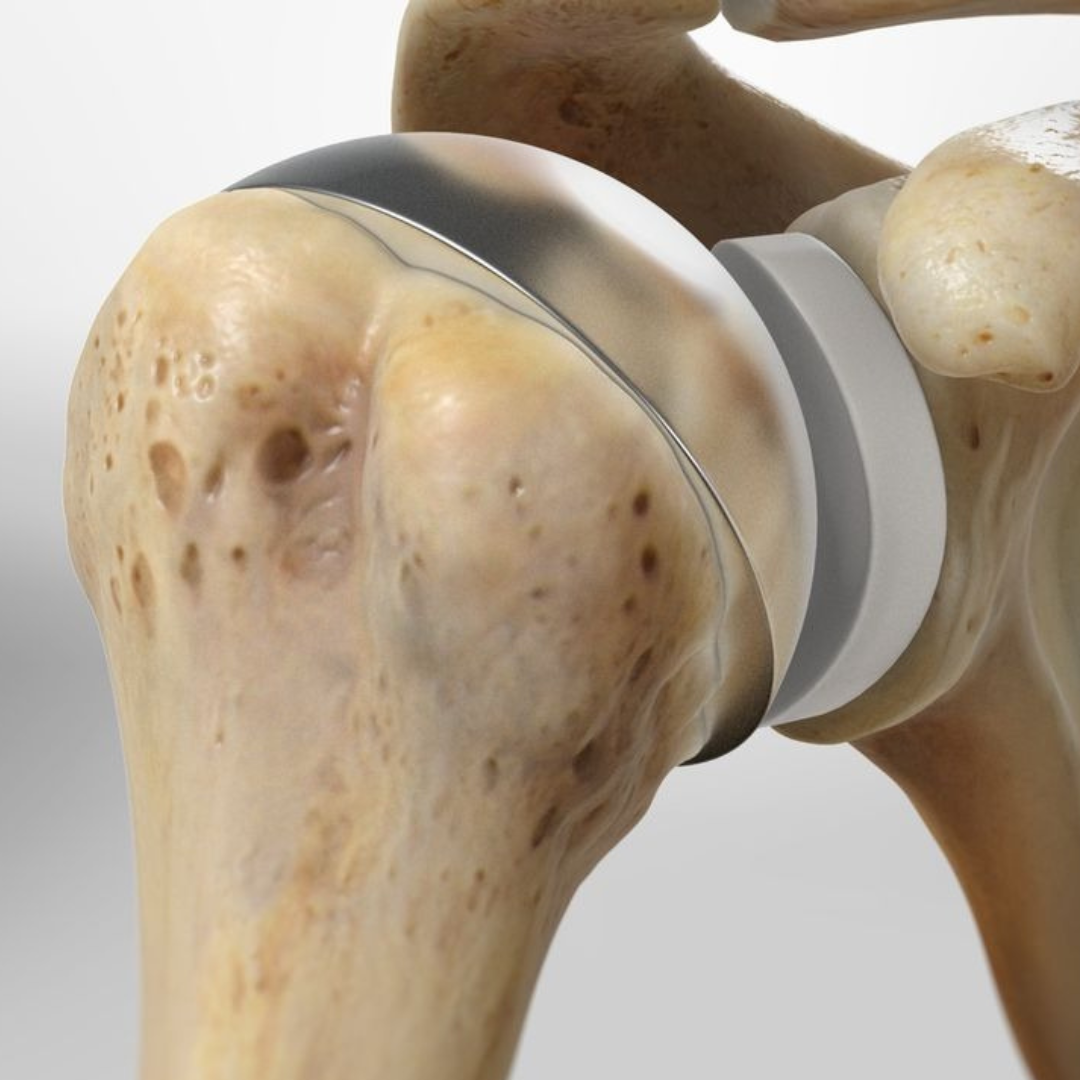

KNEE REPLACEMENT

Knee replacement or knee resurfacing can restore your desired mobility with ease. Our expert team specializes in knee replacement, with highly experienced doctors who excel in performing surgical procedures to replace damaged parts of the knee.

SHOULDER REPLACEMENT

Regain mobility and find the perfect solution for all your shoulder-related issues with shoulder replacement surgery.